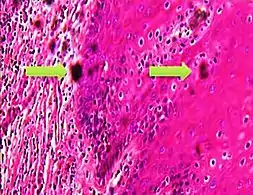

A crush artifact is an artificial elongation and distortion seen in histopathology and cytopathology studies, presumably because of iatrogenic compression of tissues. Distortion can be caused by the slightest compression of tissue and can provide difficulties in diagnosis.[2][3] It may cause chromatin to be squeezed out of nuclei.[4] Inflammatory and tumor cells are most susceptible to crush artifacts.[4]

Crush artifact from compression by forceps on the tissue sample Folding artifacts (white arrows) and a crush artifact (black arrow, with cytoplasmic hypereosinophilia and nuclear pleomorphism) from a needle.

Folding artifacts (white arrows) and a crush artifact (black arrow, with cytoplasmic hypereosinophilia and nuclear pleomorphism) from a needle.